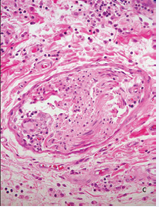

The possibility of TL, BTL, or type 1 leprosy reaction R1, was strongly suspected. PAS, Ziehl-Neelsen (ZN) and Grocott stains didn’t show germs. Small and medium sized vessels were surrounded by giant cells and lymphocytes and elastic fibers stain showed their absence or diminution in the lesion or in the vessels or their phagocytosis by the giant cells (Figure 6).

Figure 6a Medium size vein surrounded by abundant giant cells and lymphocytes.

Figure 6b Elastic stain demonstrates giant cells phagocytosing elastic fibers. A: HE, 20X. B, 40 X.

3. Giant cells surround the vessels and phagocyte the elastic fibers, which are scarce or are absent in most of the biopsy.